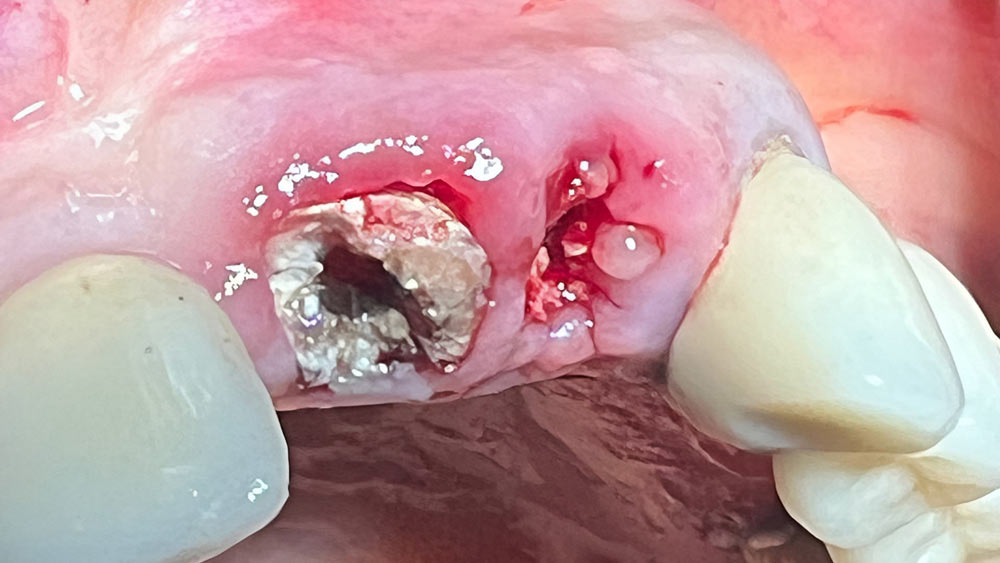

مراجعه کننده مرد 82 ساله با دو ریشه تا زیر لثه پوسیده ( 3 ) از طرف همکار دندانپزشکمان برای خارج کردن ریشه ها و کاشت دو واحد ایمپلنت به مجموعه تخصصی ما ارجاع شدند.

پس از بررسیهای بالینی و رادیولوژیک (1 ، 2 ) ، اسکن ناحیه مورد نظر انجام شد ( a4 ، b4 ) طراحی نرمافزاری محل و زاویه قرارگیری ایمپلنتها مشخص گردید ( 5 ، 6 ).

طرح درمان جراحی خارج کردن ریشهها و جراحی کاشت همزمان دو واحد ایمپلنت به انجام شد ( 7 ).